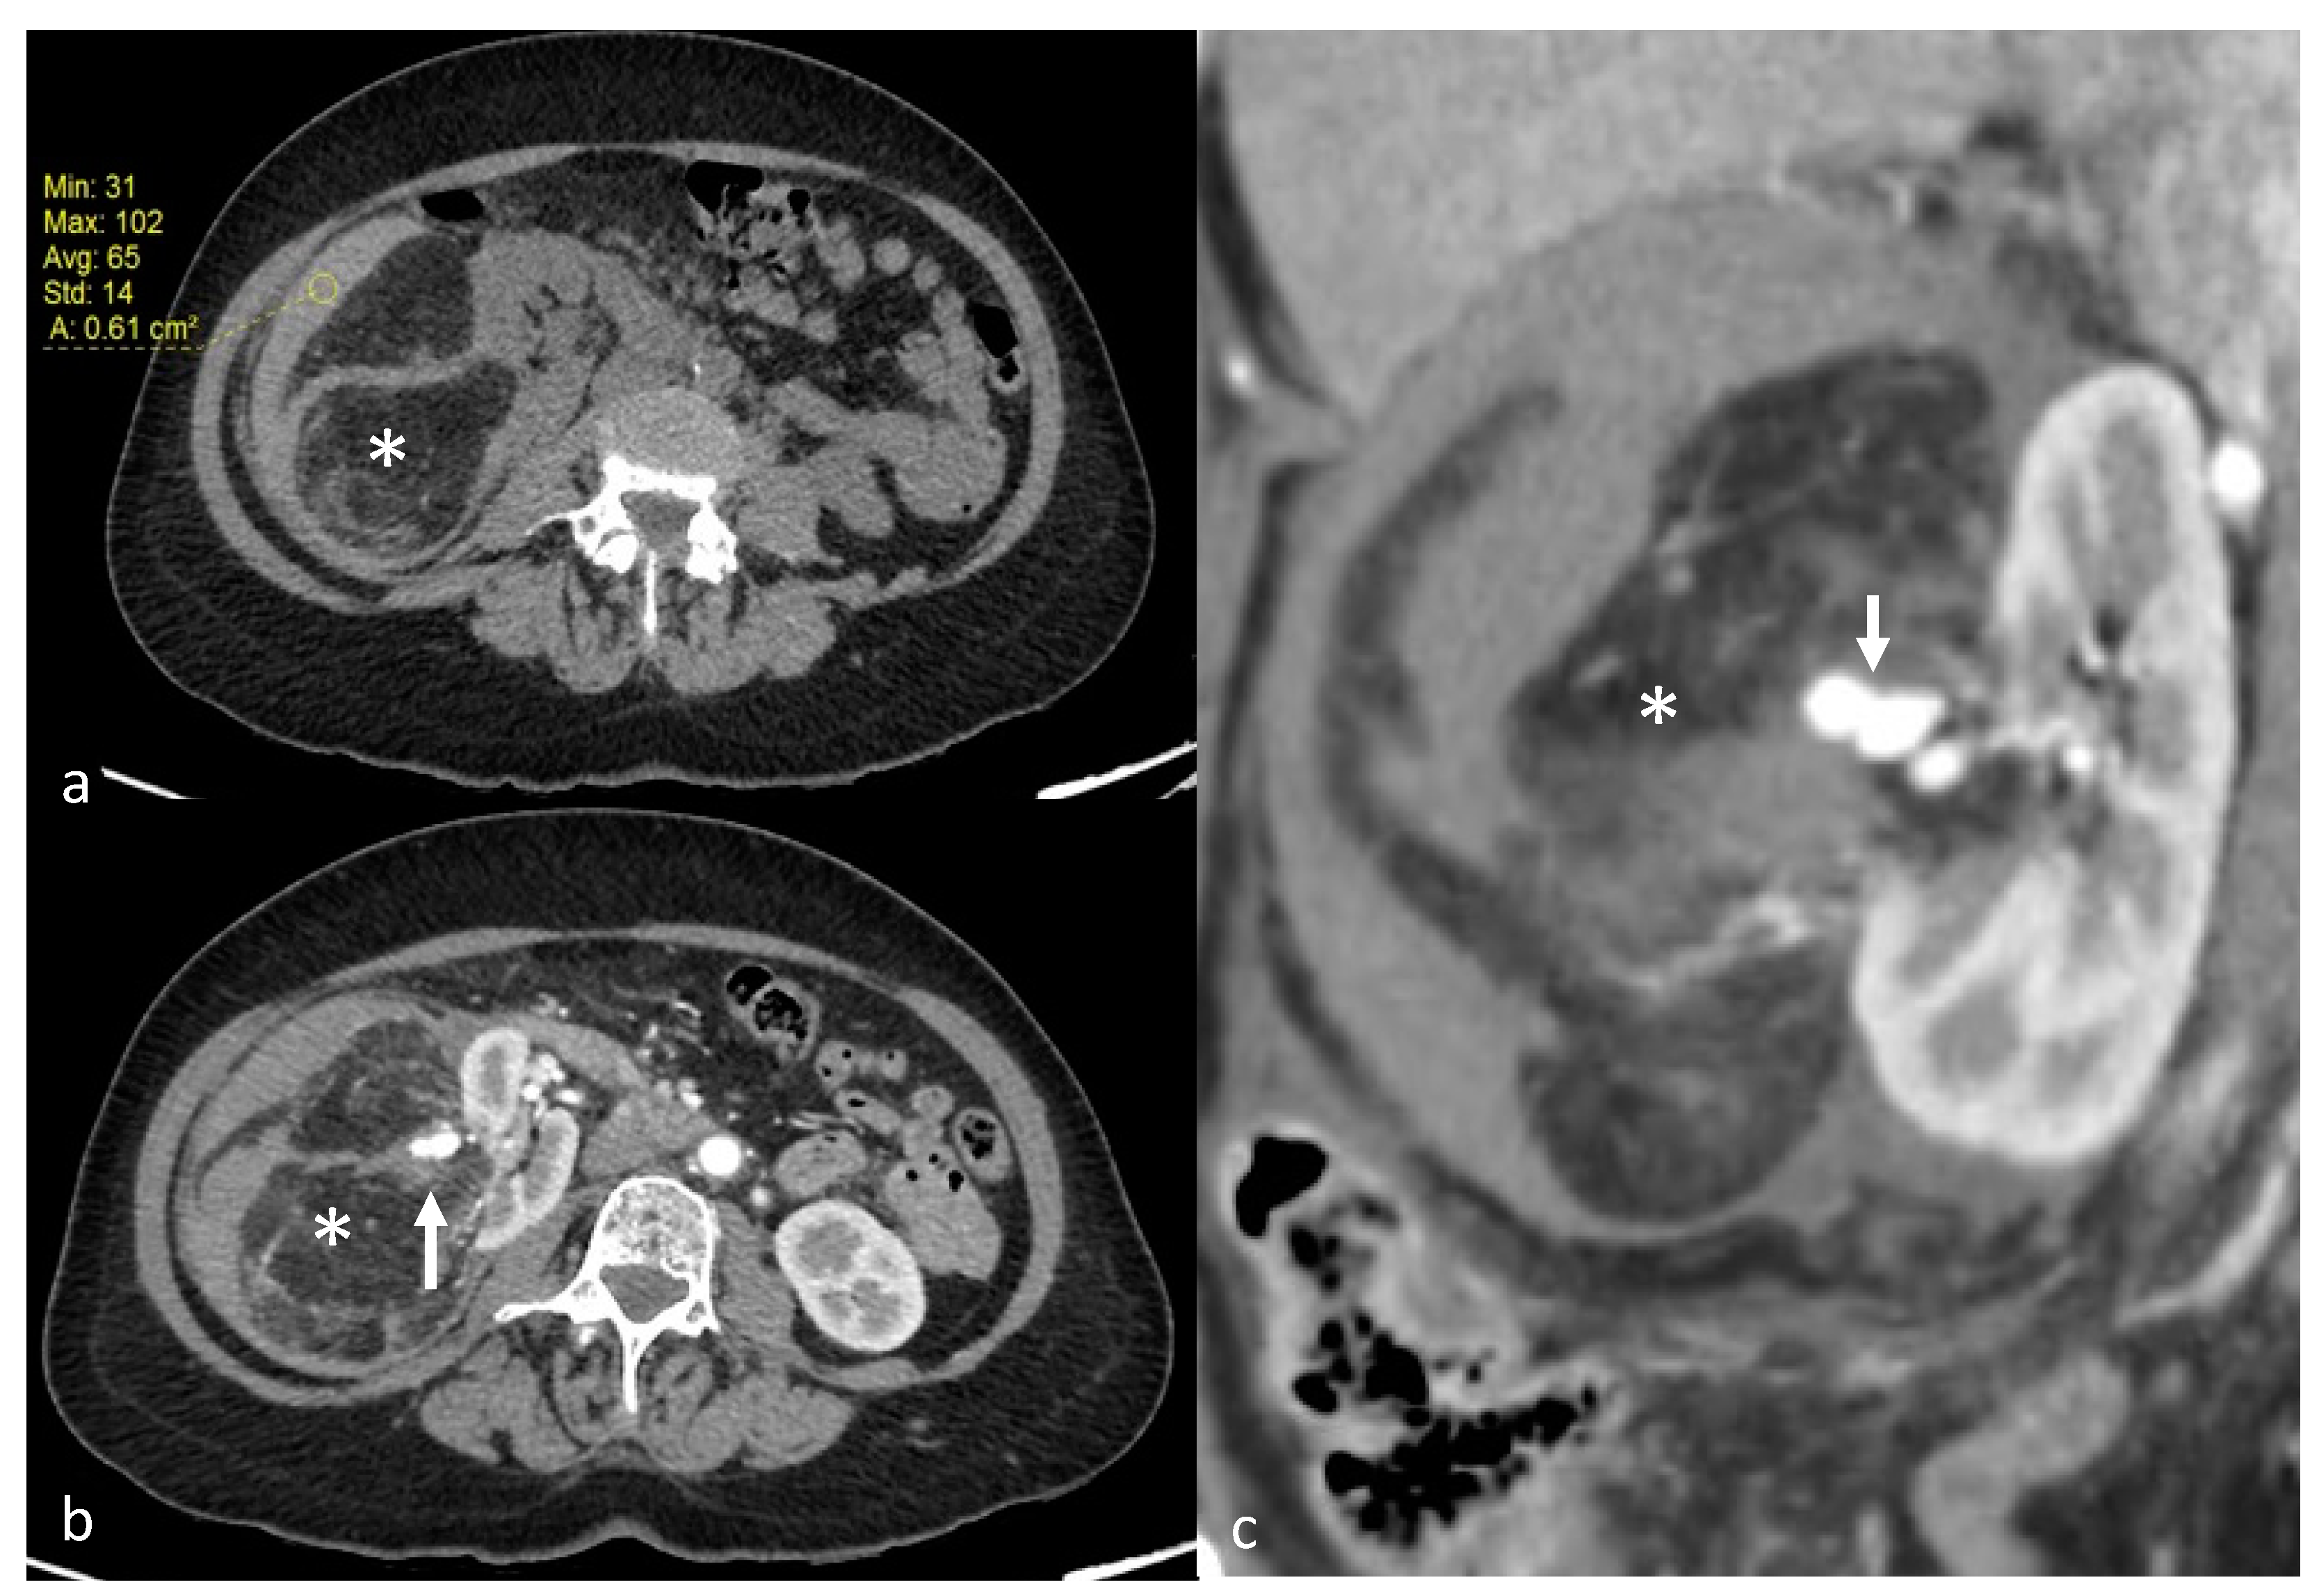

Figure 1.

A 70-year-old patient with right AML (*), Wunderlich Syndrome and aneurysm (white arrow). (a) Yellow ROI showing retroperitoneal hemorrhage (65 UH) on axial computed tomography without injection; (b) Axial computed tomography with injection and arterial acquisition; (c) Coronal computed tomography with injection and arterial acquisition.